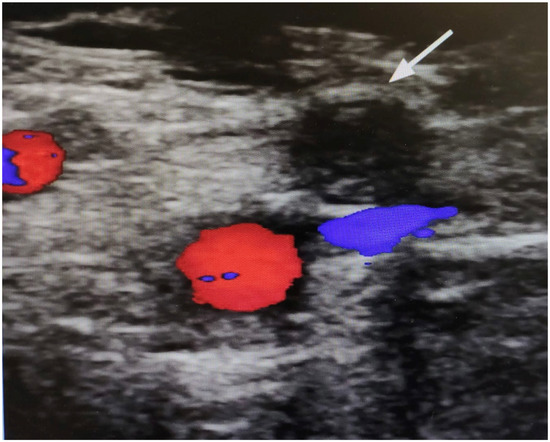

The vascular surgeon observed slight pallor and hypothermia of the right foot, leading to the suspicion of an ischemic event of the right lower limb. Moreover, a Doppler ultrasound showed complete femoral artery obstruction (Figure 3). As the patient refused an additional surgery—mainly because of lack of confidence about being hospitalized due to the COVID-19 emergency—an additional therapy with phosphodiesterase type 3 inhibitors (one capsule in the morning and one in the evening) and possible infusion of iloprost was prescribed [26,27,28,29].

Figure 3.

Doppler ultrasound image of the right thigh. The arrow highlights a complete obstruction of the superficial femoral artery. The absence of colors (red/blue) denotes a lack of flow.